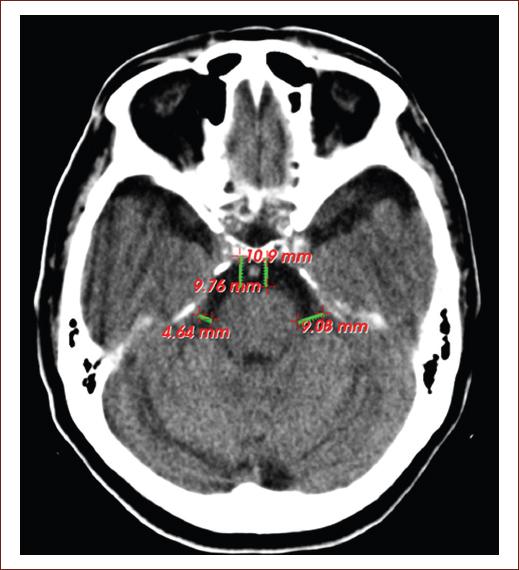

Special attention in radiological practice is given to the frontal horns of the lateral ventricles, at the level of the Monro hole, the amplitude of these in people under 40 years is < 12 mm, and in those over 40 years < 15 mm9. Dilation of the grooves (Fig. 1) and cisterns (Fig. 2) is part of the normal aging process, normal values are considered 4 mm of brain skull distance and 6 mm of interhemispheric width10. To understand structural and functional changes of the brain, research in the field of neuroscience in the 21st century has been an excellent contribution but is still insufficient4.

Figure 2 Computed tomography image of the simple skull of a 75-year-old patient, without neurologic focalization signs, it showing signs of cerebral atrophy at the level of the prechiasmatic cisterns (9.76 and 10.9 mm) and the cerebellar ponto angle (4.64 and 9.08 mm) on both sides (source: Imaging Department, Juan Bruno Zayas Alfonso Hospital).